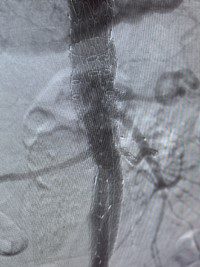

The recently FDA-approved Gore Excluder TAMBE device is an implantable branched endoprosthesis that is inserted through small incisions in the groin and just below the collarbone. Using advanced X-ray guidance, surgeons deploy multiple branches within the aorta, placing specialized stents that preserve blood flow to vital organs while redirecting pressure away from the dangerously weakened arterial walls.

The groundbreaking procedure was performed by Dr. Sternbach and Dr. William Raible of St. Peter’s Vascular Associates in March on 73-year-old Jay Tucker from Round Lake. Tucker’s aneurysm was discovered during routine screening—an especially critical find given his strong family history; his father passed away from an aortic aneurysm at age 63.